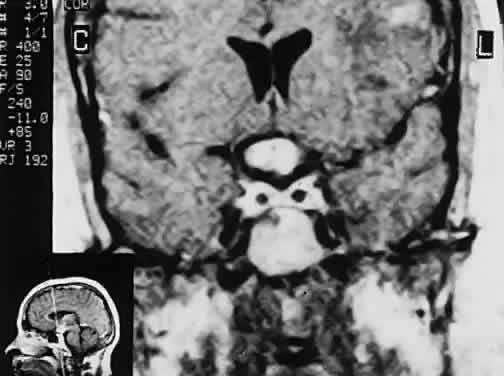

CT scanning retains special relevance to craniopharyngioma diagnosis, currently superior to MRI in detection of calcification and cyst formation (Fig. 7A to C); however, the extent of involvement of adjacent structures, that is, the optic chiasm, third ventricle, and intracavernous carotid artery, is more clearly delineated by MRI (Fig. 7D and E).93 Craniopharyngioma fluid collections are found to be uniformly bright on T2-weighted sequences, but on T1-weighted images, the signal intensity may range from hypointense to hyperintense, reflecting the heterogeneous contents of cysts. Because calcification and cyst formation are hallmarks of craniopharyngiomas, CT is more specific than MRI. At times, intrinsic infiltration of tumor may thicken the chiasm and contiguous optic nerve, a radiologic configuration that mimics glioma.94 Likewise, glioma may be simulated when the optic canal is invaded and enlarged, but accompanying bony erosion of the sella weighs heavily toward craniopharyngioma.

Fig. 7. Computed tomography scan of a large, multicystic craniopharyngioma. A. Axial section through the sella shows destruction of the bony skull base. Axial (B) and coronal (C) sections show cysts (white arrows) and calcification (arrowheads). Contrast-enhanced magnetic resonance imaging of the craniopharyngioma. Sagittal (D) and coronal (E) sections with gadolinium show solid and cystic (arrows) portions.